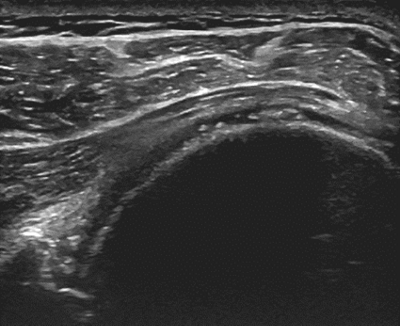

Der hochauflösende Ultraschall mit modernsten Geräten dient - ergänzend zur genauen Befragung (Anamnese) und der klinischen Untersuchung - zur Diagnose und gezielten ultraschallgesteuerten Punktion/Infiltration bei verschiedenen Erkrankungen des Bewegungsapparates.

Dabei lassen sich mittels Ultraschall strukturelle Schäden, akute Entzündungen oder sogar gestörte Bewegungsabläufe in der «dynamischen» Untersuchung darstellen. Aufgrund der ausgezeichneten Auflösung lassen sich mittlerweile auch kleinste Strukturen darstellen, punktieren und infiltrieren.